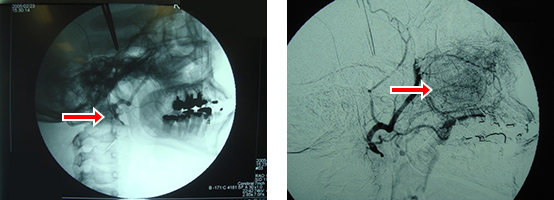

放射線治療と抗がん剤治療を併用して行った後に、手術でがんを切除する3者併用療法を基本としています。また舌がんや上顎がんでは、がんの栄養血管に直接抗がん剤を注入する治療(超選択的動注療法)を施行しており、高い効果(奏効率95%)を得られています。

動注化学療法

左:浅側頭動脈あるいは大腿動脈から外頸動脈を経て腫瘍の血管へカテーテル挿入し抗がん剤を注入

右:腫瘍血管が造影されている